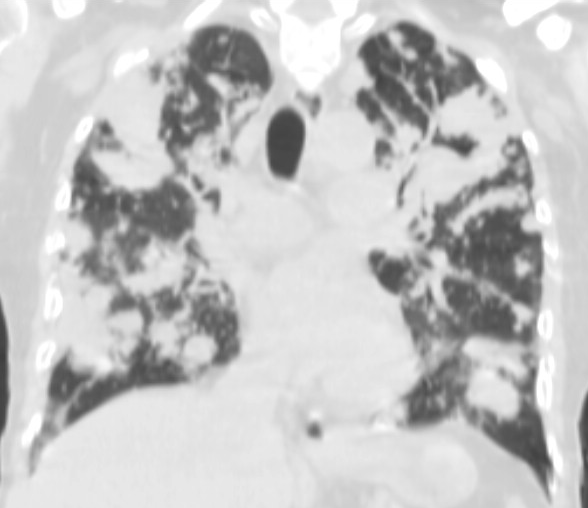

3b: Multiple lung metastasis, CT lung window (axial, coronal reformat)

Image

3c, coronal reformat

70 year old man, colon tumor.

Radiograph: Bilateral extensive, confluating patchy-nodular shadowing with diffuse reticular pattern. The diaphragm contour is partially blurry bilaterally: lymphangiosis carcinomatosa.

CT: Numerous 1-6 cm round and irregular, lobulated-spiculated contrast enhancing lesions in both lungs, everywhere sporadically.